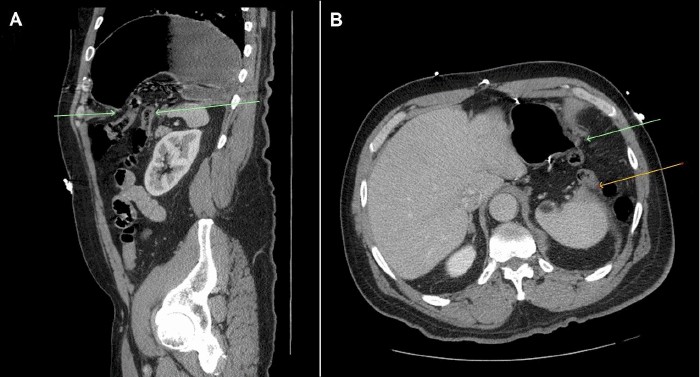

On physical examination, his abdomen was soft, non-distended, and had generalized tenderness with no guarding or rigidity. A bedside ultrasound of the abdomen did not show significant findings. Chest X ray revealed significant elevation of the left hemidiaphragm with a prominent distended gastric bubble within the left thoracic cavity (Figure 1). An abdominopelvic CT demonstrated a type IV traumatic diaphragmatic hernia on the left, which contains the splenic flexure of the colon and most of the stomach (Figure 2).

Figure 2. Abdominopelvic CT with Contrast Demonstrating Hiatal Hernia Containing Splenic Flexure and Stomach in A) Sagittal Section and B) Axial Section. Published with Permission

The intrathoracic stomach within the hernia was dilated with air and fluid; however, there was no transition point indicating evidence of obstruction. Nasogastric decompression and fluid resuscitation were implemented, and after careful counseling and consent, the patient was taken to the operating room for planned transabdominal laparoscopic repair of the diaphragmatic hernia. Upon laparoscopic entry into the abdomen, dense adhesions were found in the upper abdomen, consistent with the patient's prior open repair of a perforated gastric ulcer. This made the entire upper abdomen technically difficult to dissect out and identify anatomy. Extensive intraabdominal lysis of adhesions was required to visualize the hernia. The defect measured 9.5 cm transversely and 4.5 cm in the anterior-posterior dimension. Upon reduction of the hernia, the left lung was noted to be severely atelectatic; it expanded eventually with ventilation. A relaxing incision in the diaphragm was made, and the defect closed transversely with several non-absorbable v-lock sutures. The repair was then reinforced with onlay absorbable mesh (Phasix ST) (Figure 3).